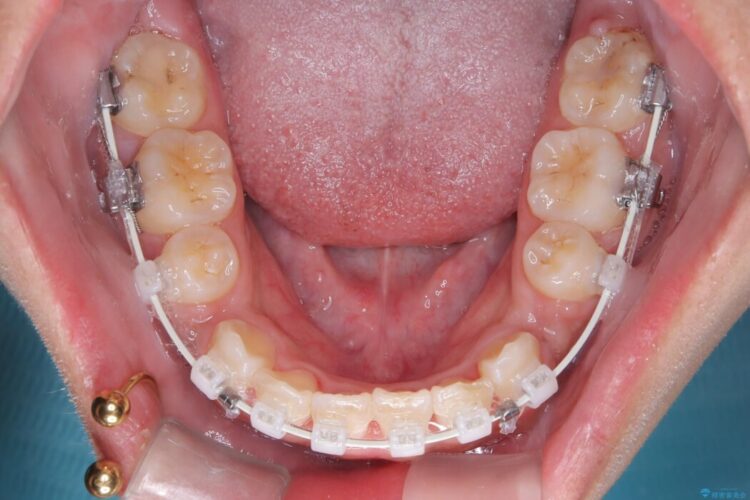

- 矯正装置:ワイヤー(審美装置)

無理に歯を並べても口元の突出感は解消されないため、上下左右4番を抜歯しスペースを確保、目立ちにくい審美ワイヤー装置にて治療を行うこととしました。

抜歯によって得たスペースを活用し、審美ワイヤーによる繊細な角度調整を行いながら前歯を後方へ移動。